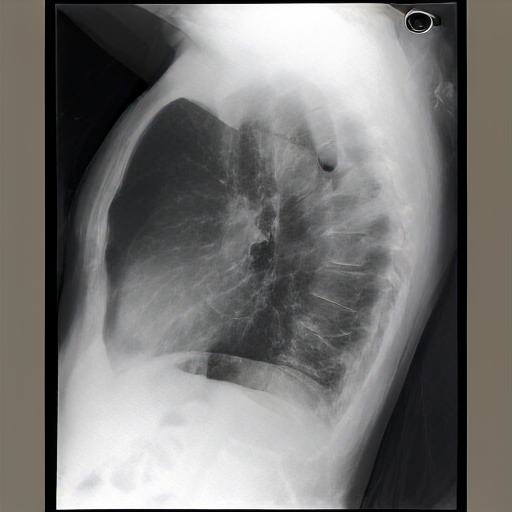

As compared to the previous radiograph, there is pneumonia in the right upper lobe, better visible on the lateral radiograph and moderately dense on the frontal radiograph, appearing more extensive. A newly appeared retrocardiac lung opacity suggests possible re-expansion by a malignancy. A pre-existing lung opacity in the left retrocardiac region has increased substantially. The opacity is likely large, potentially pneumonia in the lateral location. The opacity is confirmed on both the lateral and frontal radiographs, consistent with the clinical presentation.